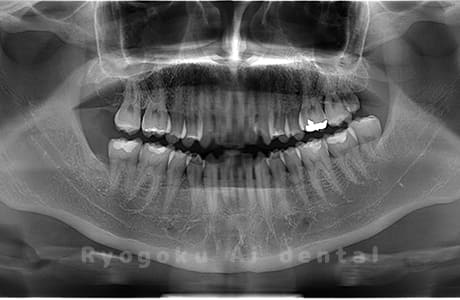

Case10

- 下顎左の親知らず

- 下顎左の親知らずを抜歯したケースです。

<リスク・副作用>

手術後は痛み、腫れ、痺れなどの副作用が生じる場合があります。